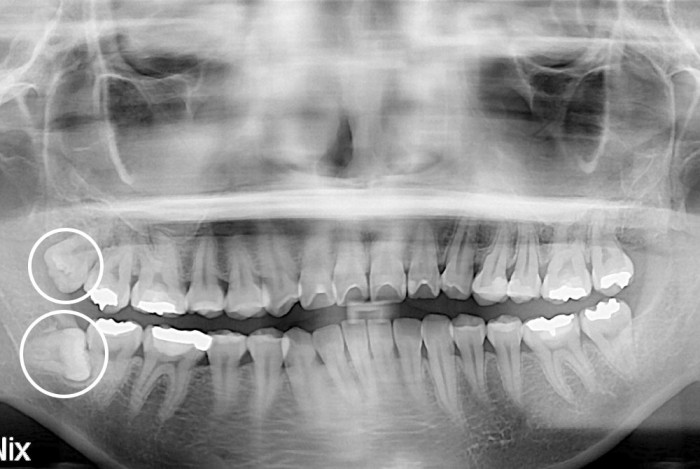

[사랑니] 사랑니

치료전 : 2019-10-16

세종치과는 구강악안면외과학 박사이신 원장님이 발치하는 치과입니다.